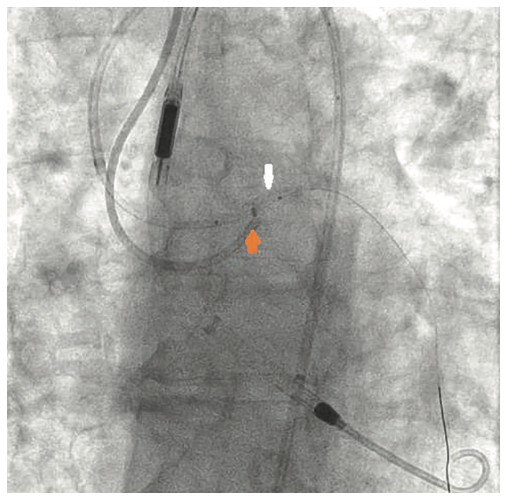

The right groin was accessed using fluoroscopic guidance. A micropuncture sheath was placed and upsized to a 7 French, 45 cm Destination sheath (Terumo) in the right groin. We accessed the right radial, but could not get good flow. Therefore, we ended up using the ulnar artery with ultrasound guidance and placed a Terumo 5/6 Slender sheath in the ulnar artery. We proceeded to access the left axillary artery. We placed a Judkins right (JR)4 catheter in the left subclavian and did a selective angiogram, documenting the location of the thoracoacromial artery and circumflex humeral (Figure 4); then using a Chiba biopsy needle (Cook), accessed the axillary artery and placed a 5-French 30 cm sheath (Cook)(Figure 5). We used the 15 cm biopsy needle to allow us a shallow angle of approach with the patient’s body habitus and to avoid “kinking” the sheath. We then switched out for the Lunderquist wire (Cook Medical), placed an 8 Fr sheath, and performed a pre-close using two Perclose devices (Abbott Vascular) (Figure 6).

What anatomical landmarks do you look for when accessing the axillary artery?

Ideally, the axillary artery should be accessed in the second portion, which runs behind the pectoralis minor muscle. This is clinically important, since it is associated with the lowest chance of causing brachial plexus injury. These landmarks are often seen using ultrasound imaging. However, our practice is to use selective angiogram of the subclavian and axillary arteries. Once the axillary artery and all branches are defined, the access point should be lateral to the thoracoacromial artery and medial to the circumflex humeral arteries (Figures 22-23). We recommend a shallow angle of approach, since the Impella sheath is prone to kinking; alternatively, a Cook 14 Fr x 13 cm sheath can be used for the Impella 2.5 or a Cook 14 Fr x 30 cm sheath for the Impella CP.

- Angiographic assessment of the axillary artery and all branches is an important step to define an access point that is lateral to the thoracoacromial artery and medial to the circumflex humeral artery (Figures 22-23).